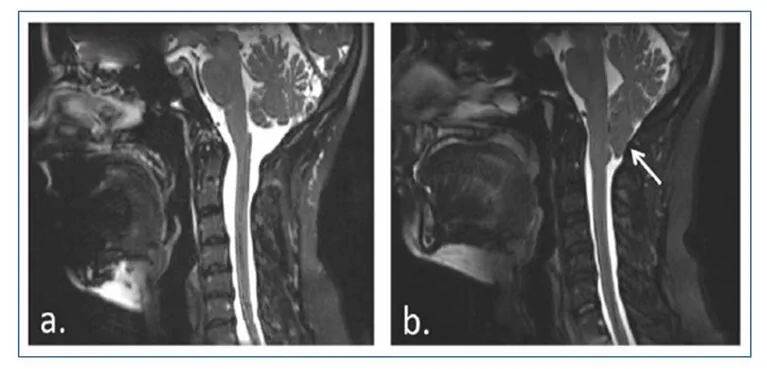

Chiari malformation type I involves a caudal herniation of the cerebellar tonsils of approximately 5 mm below the foramen magnum, which is not usually accompanied by descent of the brainstem or the fourth ventricle nor by hydrocephalus, but it is associated with syringomyelia.

Girl diagnosed with Chiari malformation type I, with syringomyelia, surgically operated on at 12 years of age.